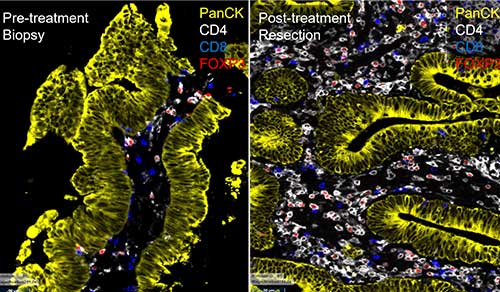

NewYork-Presbyterian cancer specialists are at the forefront of expanding and innovating treatment for everything from breast cancer to glioblastoma. In 2025, our physicians and researchers from Columbia and Weill Cornell Medicine improved progression-free survival for multiple types of cancer, employed artificial intelligence to inform clinical care, discovered biomarkers that predict treatment responses to help personalize care in complex cases, and more. These advancements are breaking ground for new solutions that can improve cancer outcomes for all patients.

Through two world-class cancer centers – Columbia’s NCI-designated Herbert Irving Comprehensive Cancer Center and Weill Cornell Medicine’s Meyer Cancer Center, our team of physician-scientists are transforming care for cancer patients across a broad spectrum of malignant diseases and conditions. From pursuing novel laboratory research to better predict, diagnose and treat cancer, to conducting clinical trials of promising new therapies, our physicians provide personalized treatment plans to deliver optimal outcomes.